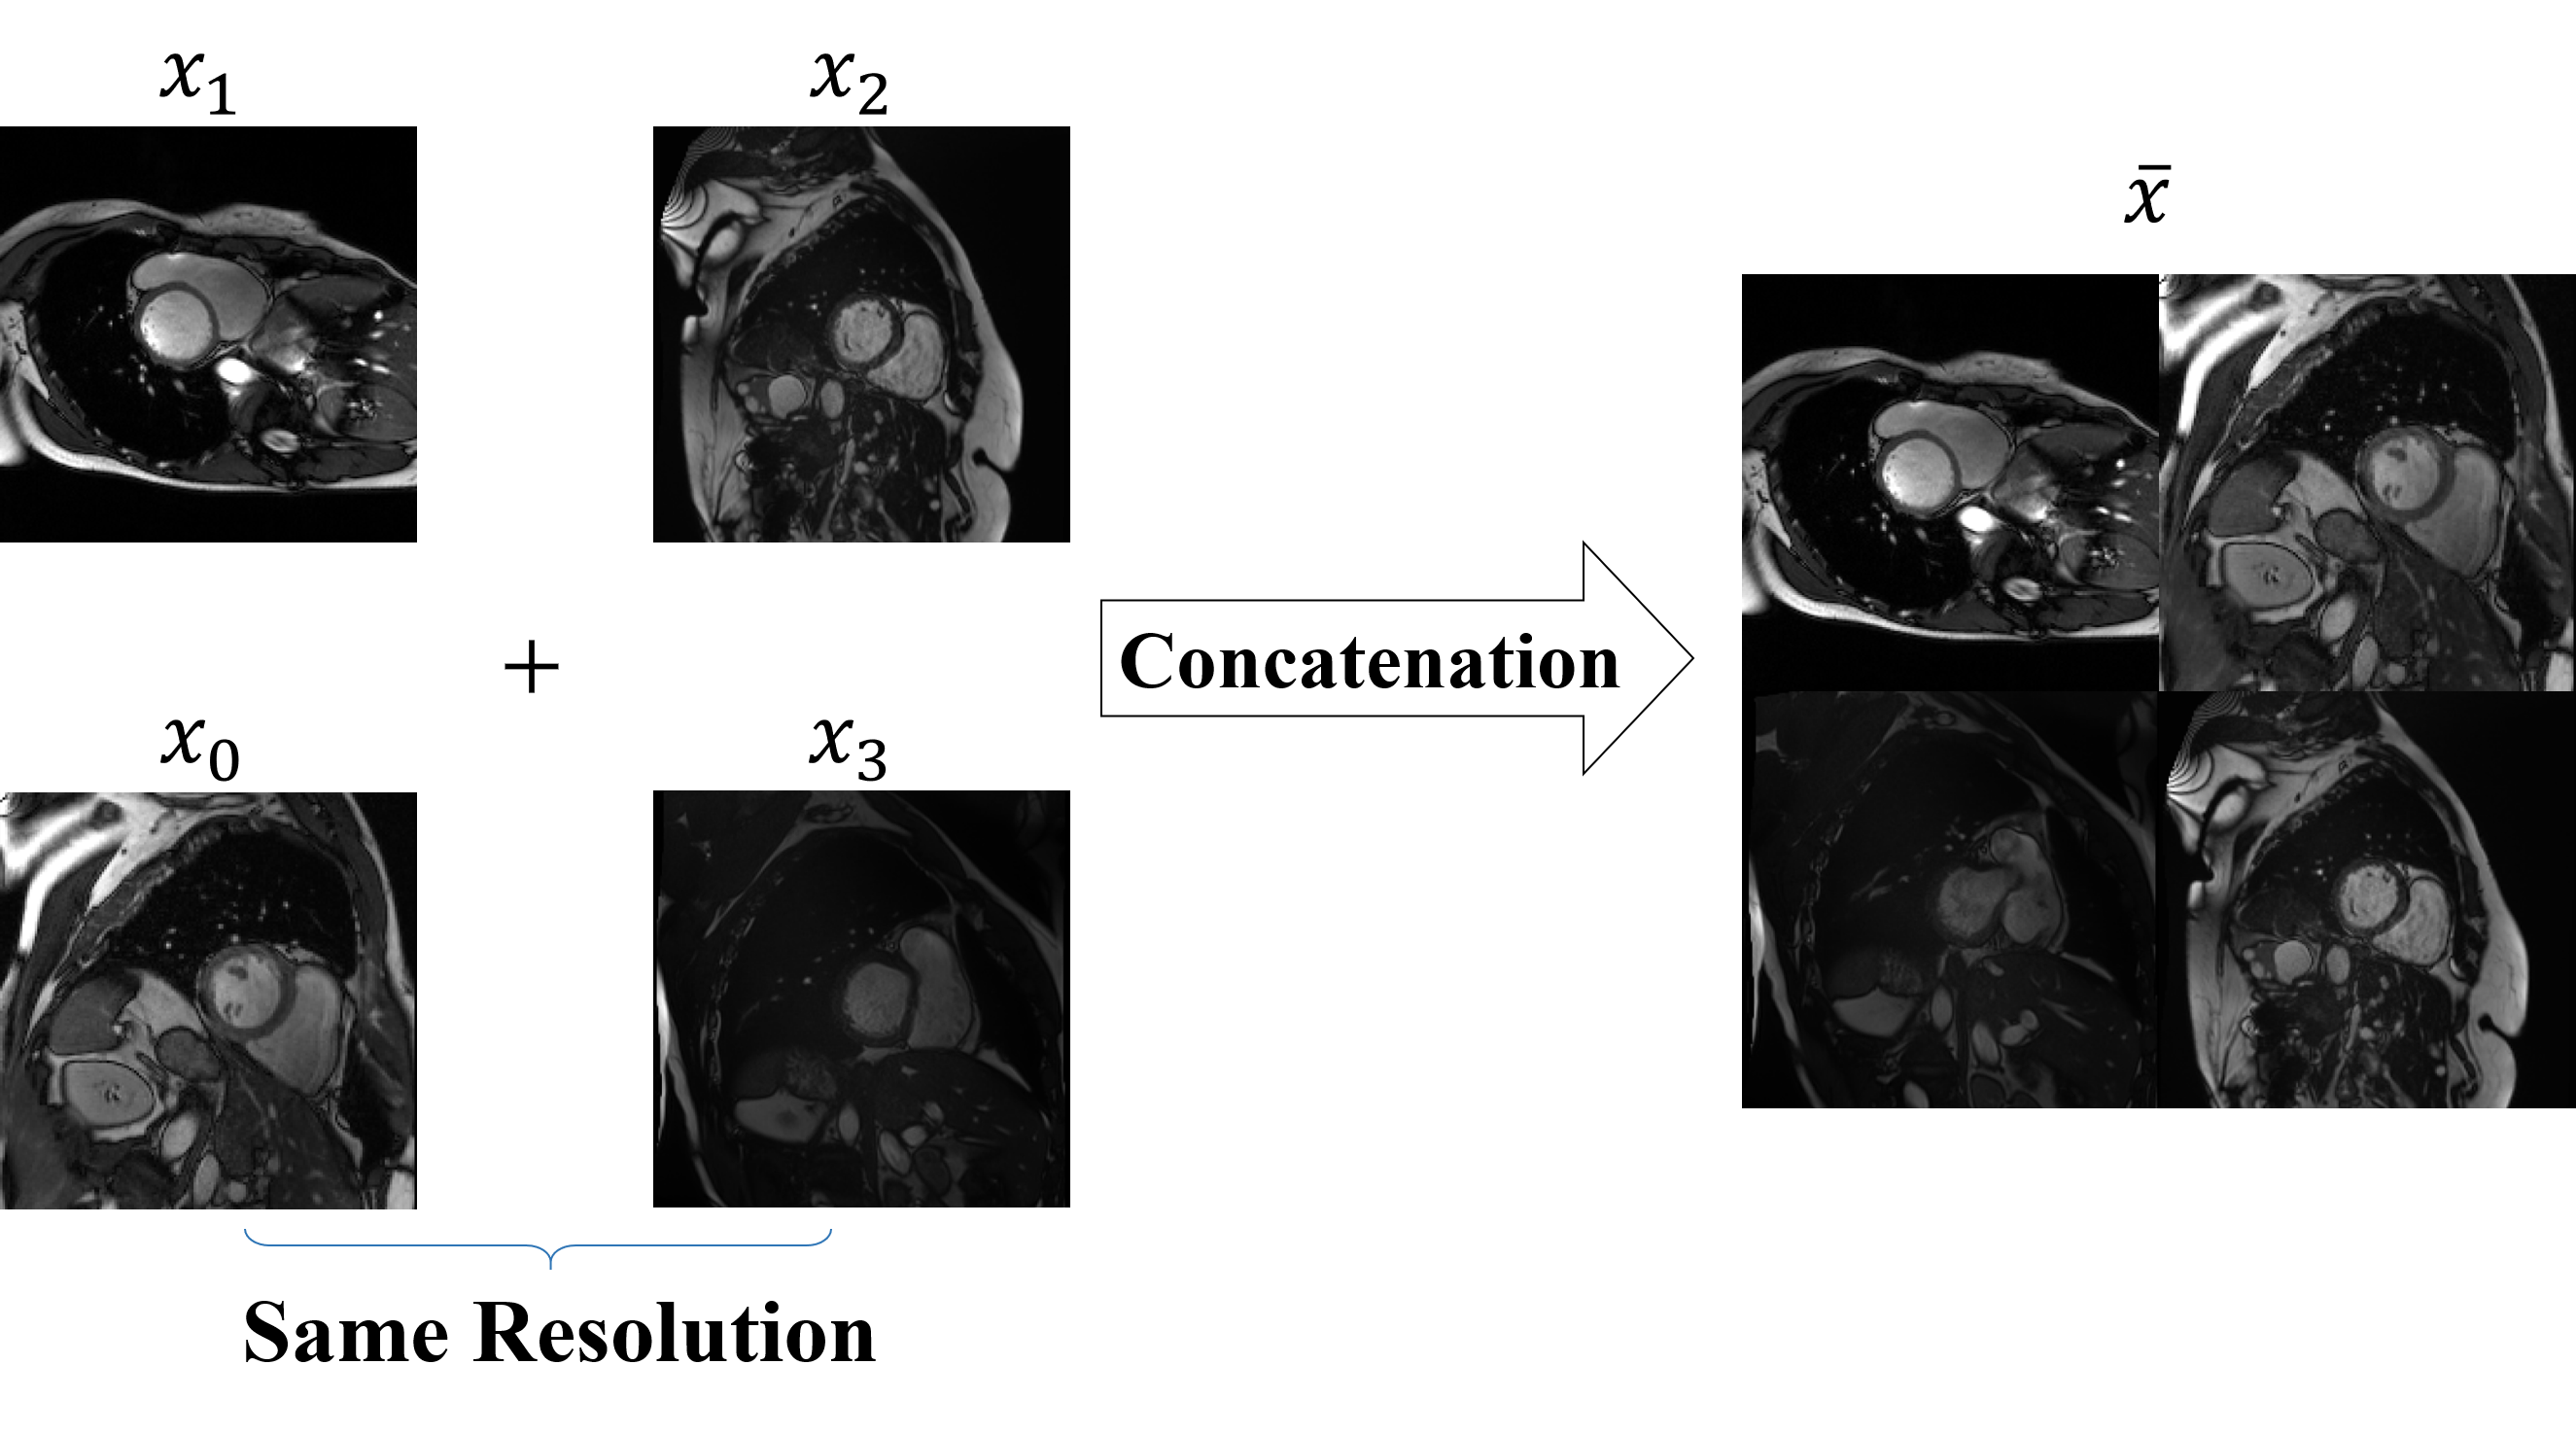

Figure 3: Illustration of Scaling-up Mix, an important part of SM22{}^{2}start_FLOATSUPERSCRIPT 2 end_FLOATSUPERSCRIPTC. Scaling-up Mix creates images with increased foreground-background diversity by concatenating four images.

Beyond batch size adaptation, we argue that enriching the context of individual images has the potential to strength-en the network’s ability to learn semantic features and mitigate overfitting. Our approach involves concatenating four different images to construct a novel input image characterized by increased size and more complex context, as visually illustrated in Figure 3. The scaling procedure can be formalized as follows:

x¯=Concat(x0,x1,x2,x3)¯𝑥Concatsubscript𝑥0subscript𝑥1subscript𝑥2subscript𝑥3\displaystyle\overline{x}={\rm Concat}(x_{0},x_{1},x_{2},x_{3})over¯ start_ARG italic_x end_ARG = roman_Concat ( italic_x start_POSTSUBSCRIPT 0 end_POSTSUBSCRIPT , italic_x start_POSTSUBSCRIPT 1 end_POSTSUBSCRIPT , italic_x start_POSTSUBSCRIPT 2 end_POSTSUBSCRIPT , italic_x start_POSTSUBSCRIPT 3 end_POSTSUBSCRIPT ) (1)

Where x0subscript𝑥0x_{0}italic_x start_POSTSUBSCRIPT 0 end_POSTSUBSCRIPT, x1subscript𝑥1x_{1}italic_x start_POSTSUBSCRIPT 1 end_POSTSUBSCRIPT, x2subscript𝑥2x_{2}italic_x start_POSTSUBSCRIPT 2 end_POSTSUBSCRIPT and x3subscript𝑥3x_{3}italic_x start_POSTSUBSCRIPT 3 end_POSTSUBSCRIPT are 4 randomly selected images from the dataset Dusubscript𝐷𝑢D_{u}italic_D start_POSTSUBSCRIPT italic_u end_POSTSUBSCRIPT, resized to the same size before training, and we use Concat()Concat\rm Concat()roman_Concat ( ) to mix the images together. The image x¯¯𝑥\overline{x}over¯ start_ARG italic_x end_ARG is four times the size of the image xiDusubscript𝑥𝑖subscript𝐷𝑢x_{i}\in D_{u}italic_x start_POSTSUBSCRIPT italic_i end_POSTSUBSCRIPT ∈ italic_D start_POSTSUBSCRIPT italic_u end_POSTSUBSCRIPT. In particular, training the networks becomes more difficult because x¯¯𝑥\overline{x}over¯ start_ARG italic_x end_ARG contains 4 groups of segmentation objects, and the networks have to recognize more objects in a larger context, which avoids the possibility of missing objects of a certain category in an input image, as well as increasing the diversity of images in model training.